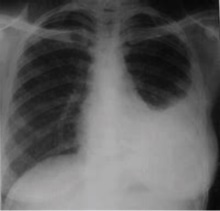

Chest x-ray of pleural thickening post-primary tuberculosis

1. Pleural thickening - Irregularity or abnormal prominence of the pleural margin, including apical capping (thickening of the pleura in the apical region). Pleural thickening can be calcified.

3. Blunting of costophrenic angle (in adults)—Loss of sharpness of one or both costophrenic angles. Blunting can be related to a small amount of fluid in the pleural space or to pleural thickening and, by itself, is a non-specific finding (except in children, when even minor blunting may suggest active TB). In contrast a large pleural effusion, or the presence of a significant amount of fluid in the pleural space, may be a sign of active TB at any age.